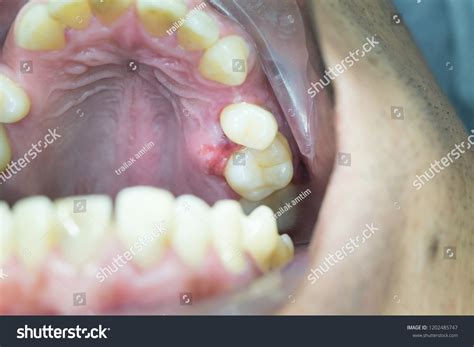

A swollen mouth palate, or oral mucosal swelling, occurs when the soft tissue on the roof of the mouth becomes inflamed and enlarged. This condition can affect anyone, regardless of age, and can be caused by a multitude of factors. The palate is a crucial part of the oral cavity, playing a significant role in speech, swallowing, and breathing. When it becomes swollen, it can disrupt these functions and cause discomfort.

Trauma

Physical trauma to the mouth can result in a swollen mouth palate. This can occur from:

• Accidental bites or injuries.

• Dental procedures or surgeries.

• Burns from hot food or drinks.